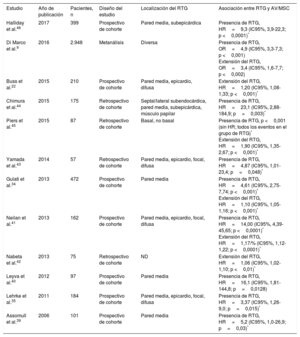

Estudios que informan del riesgo de arritmias ventriculares y muerte súbita cardiaca asociado con el realce tardío de gadolinio en pacientes con miocardiopatía dilatada

| Estudio | Año de publicación | Pacientes, n | Diseño del estudio | Localización del RTG | Asociación entre RTG y AV/MSC |

|---|---|---|---|---|---|

| Halliday et al.46 | 2017 | 399 | Prospectivo de cohorte | Pared media, subepicárdica | Presencia de RTG, HR=9,3 (IC95%, 3,9-22,3; p <0,0001)* |

| Di Marco et al.9 | 2016 | 2.948 | Metanálisis | Diversa | Presencia de RTG, OR=4,9 (IC95%, 3,3-7,3; p <0,001) Extensión del RTG, OR=3,4 (IC95%, 1,6-7,7; p <0,002) |

| Buss et al.22 | 2015 | 210 | Prospectivo de cohorte | Pared media, epicardio, difusa | Extensión del RTG, HR=1,20 (IC95%, 1,08-1,33; p <0,001)* |

| Chimura et al.44 | 2015 | 175 | Retrospectivo de cohorte | Septal/lateral subendocárdica, pared media, subepicárdica, músculo papilar | Presencia de RTG, HR=23,1 (IC95%, 2,88-184,9; p=0,003)* |

| Piers et al.45 | 2015 | 87 | Retrospectivo de cohorte | Basal, no basal | Presencia de RTG, p <0,001 (sin HR; todos los eventos en el grupo de RTG)* Extensión del RTG, HR=1,90 (IC95%, 1,35-2,67; p <0,001)* |

| Yamada et al.43 | 2014 | 57 | Retrospectivo de cohorte | Pared media, epicardio, focal, difusa | Presencia de RTG, HR=4,87 (IC95%, 1,01-23,4; p=0,048)* |

| Gulati et al.34 | 2013 | 472 | Prospectivo de cohorte | Pared media | Presencia de RTG, HR=4,61 (IC95%, 2,75-7,74; p <0,001)* Extensión del RTG, HR=1,10 (IC95%, 1,05-1,16; p <0,001)* |

| Neilan et al.41 | 2013 | 162 | Prospectivo de cohorte | Pared media, epicardio, focal, difusa | Presencia de RTG, HR=14,00 (IC95%, 4,39-45,65; p <0,0001)* Extensión del RTG, HR=1,17/% (IC95%, 1,12-1,22; p <0,0001)* |

| Nabeta et al.42 | 2013 | 75 | Retrospectivo de cohorte | ND | Extensión del RTG, HR=1,06 (IC95%, 1,02-1,10; p <0,01)* |

| Leyva et al.40 | 2012 | 97 | Prospectivo de cohorte | Pared media | Presencia de RTG, HR=16,1 (IC95%, 1,81-144,8; p=0,0128) |

| Lehrke et al.35 | 2011 | 184 | Prospectivo de cohorte | Pared media, epicardio, focal, difusa | Presencia de RTG, HR=3,37 (IC95%, 1,26-9,0; p=0,015)* |

| Assomull et al.39 | 2006 | 101 | Prospectivo de cohorte | Pared media | Presencia de RTG, HR=5,2 (IC95%, 1,0-26,9; p=0,03)* |

AV: arritmias ventriculares; HR: hazard ratio; IC95%: intervalo de confianza del 95%; MSC: muerte súbita cardiaca; ND: no disponible; OR: odds ratio; RTG: realce tardío de gadolinio.